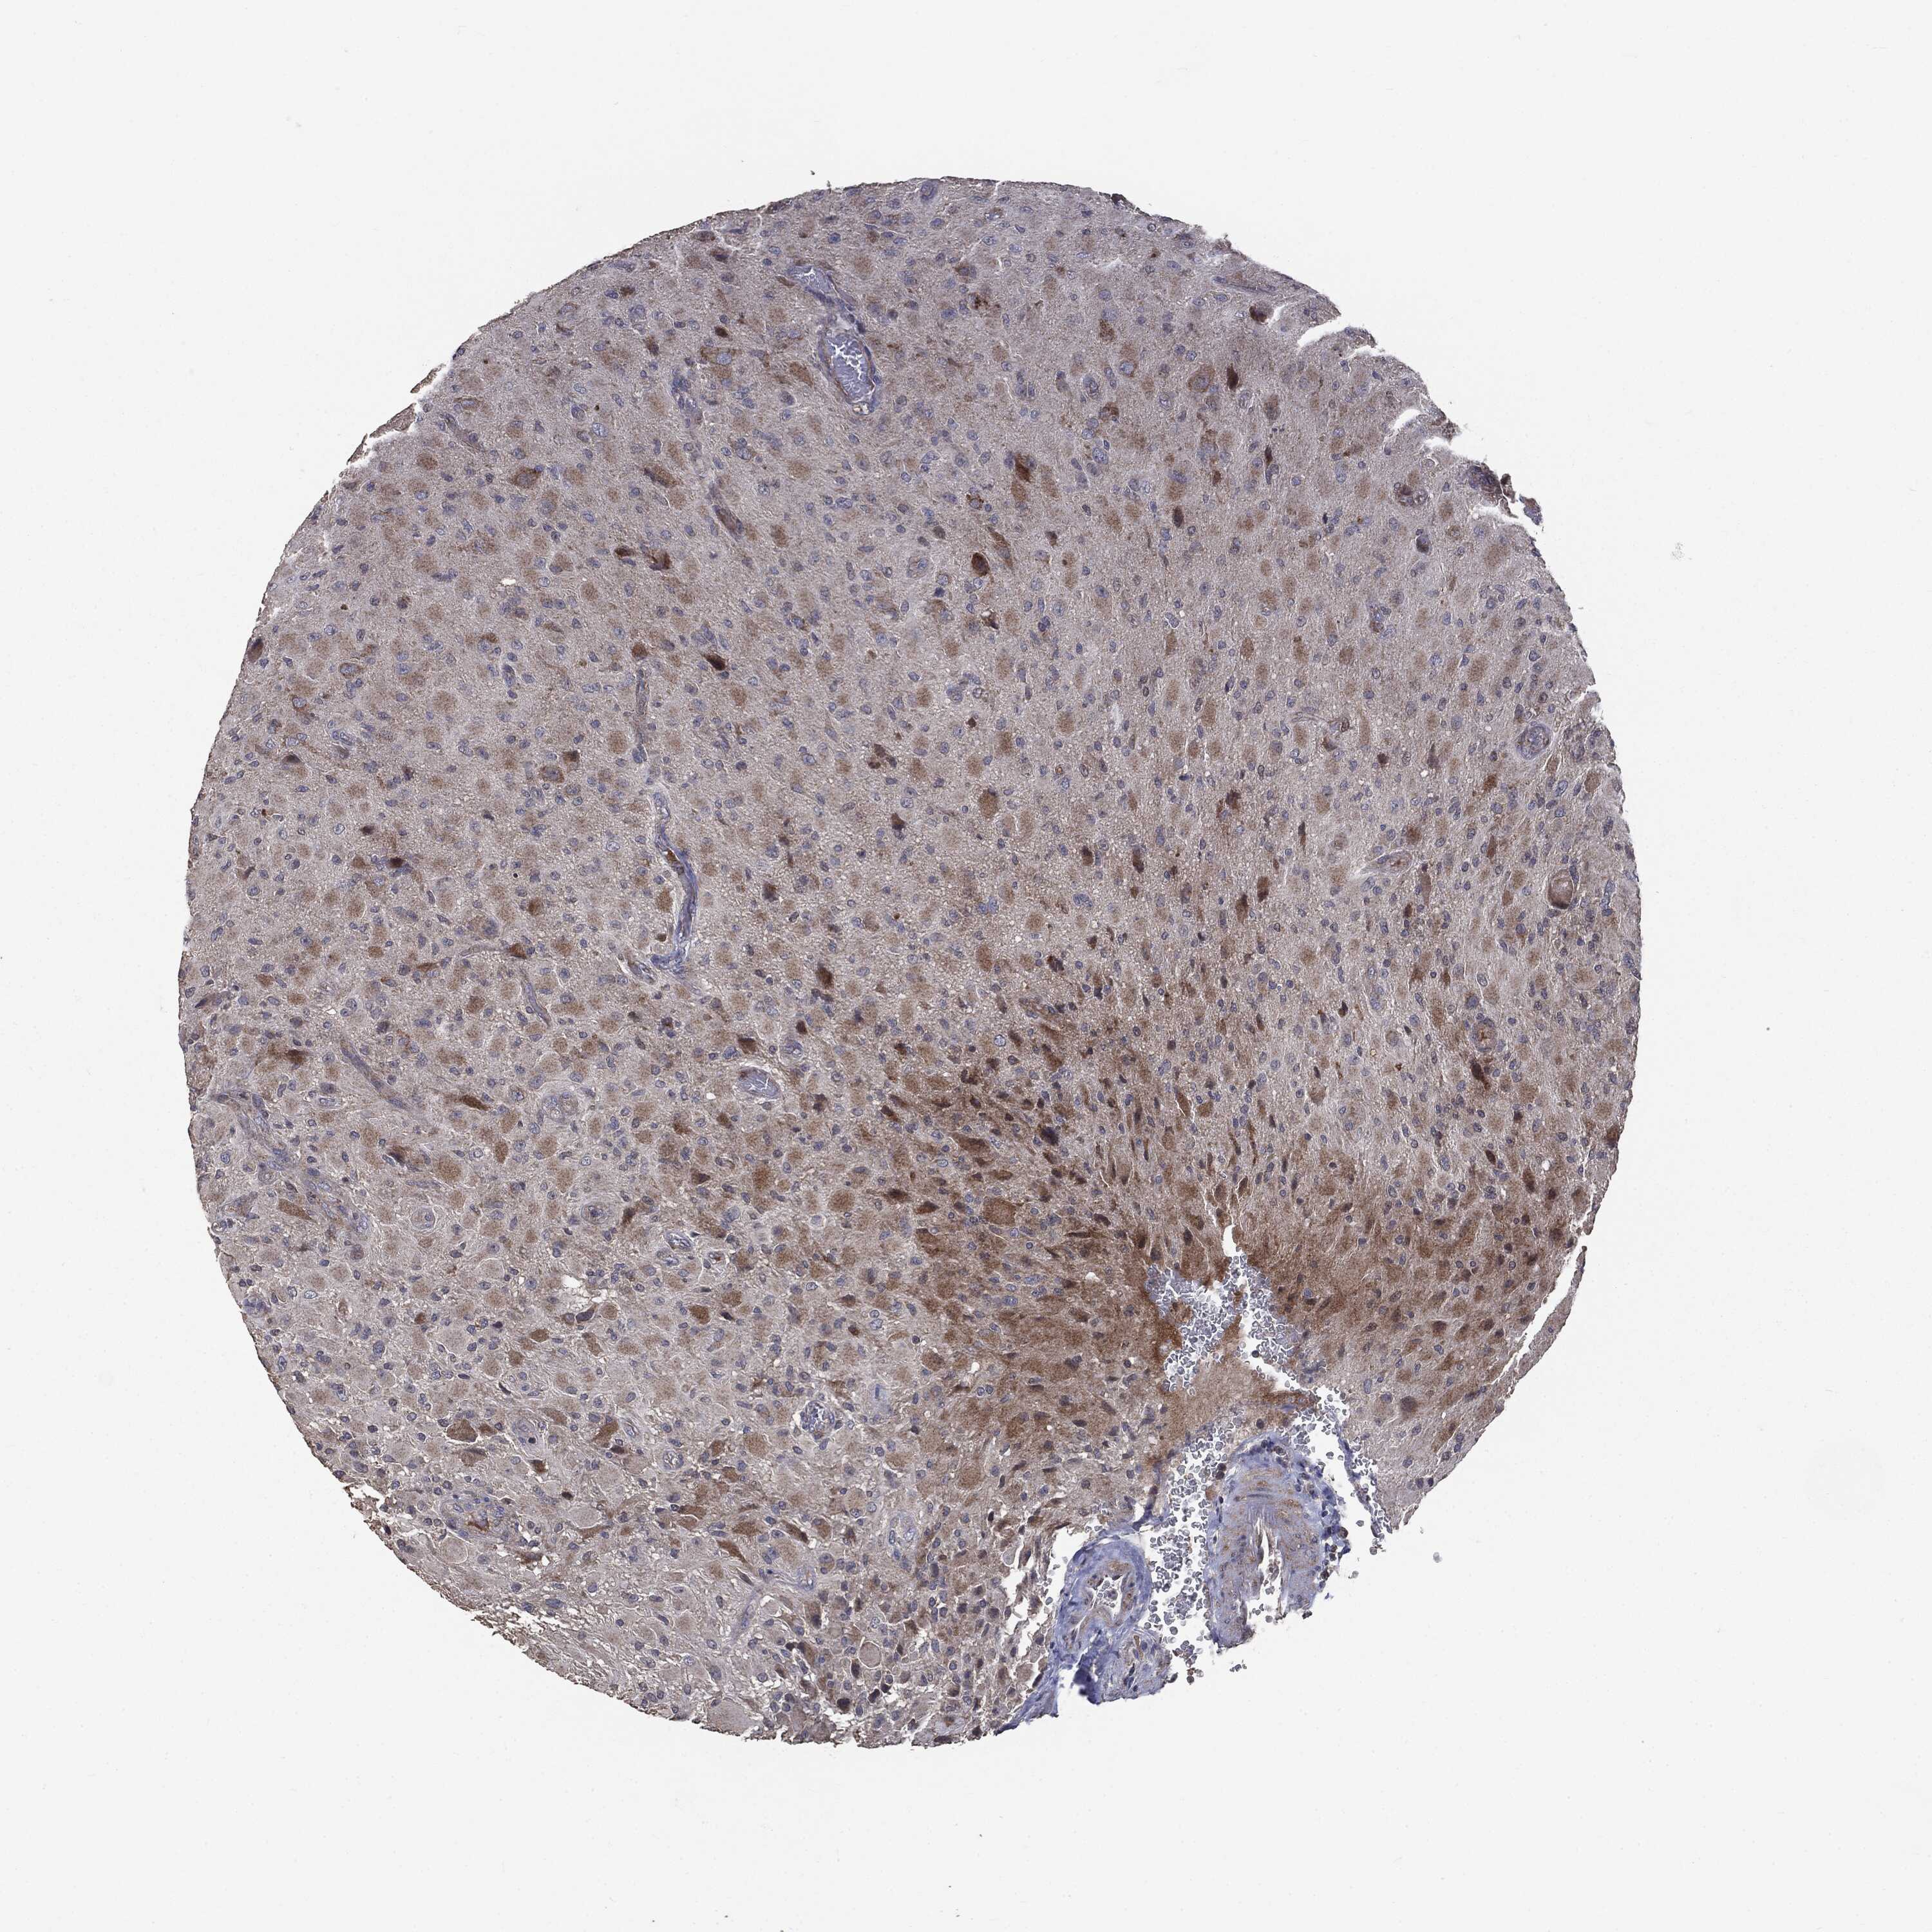

GLIOMA - Protein expressioni

A mouse-over function shows sample information and annotation data. Click on an image to view it in a full screen mode. Samples can be filtered based on level of antibody staining by selecting one or several of the following categories: high, medium, low and not detected. The assay and annotation is described here.

Note that samples used for immunohistochemistry by the Human Protein Atlas do not correspond to samples in the TCGA dataset.

Antibody stainingi

Antibody staining in the annotated cell types in the current human tissue is reported as not detected, low, medium, or high, based on conventional immunohistochemistry profiling in selected tissues. This score is based on the combination of the staining intensity and fraction of stained cells.

Each image is clickable and will lead to virtual microscopy that enables deeper exploration of all samples and also displays staining intensity scores, fraction scores and subcellular localization as well as patient and tissue information for each sample.

CAB069425

CAB080053

CAB080065

CAB080070

CAB080081

CAB080095

CAB080097

Staining

High

Medium

Low

Not detected

Intensity

Strong

Moderate

Weak

Negative

Quantity

>75%

75%-25%

<25%

None

Location

Nuclear

Cytoplasmic/membranous

Cytoplasmic/membranous,nuclear

Glioma, malignant, Low grade

Glioma, malignant, High grade

Glioma, malignant, NOS